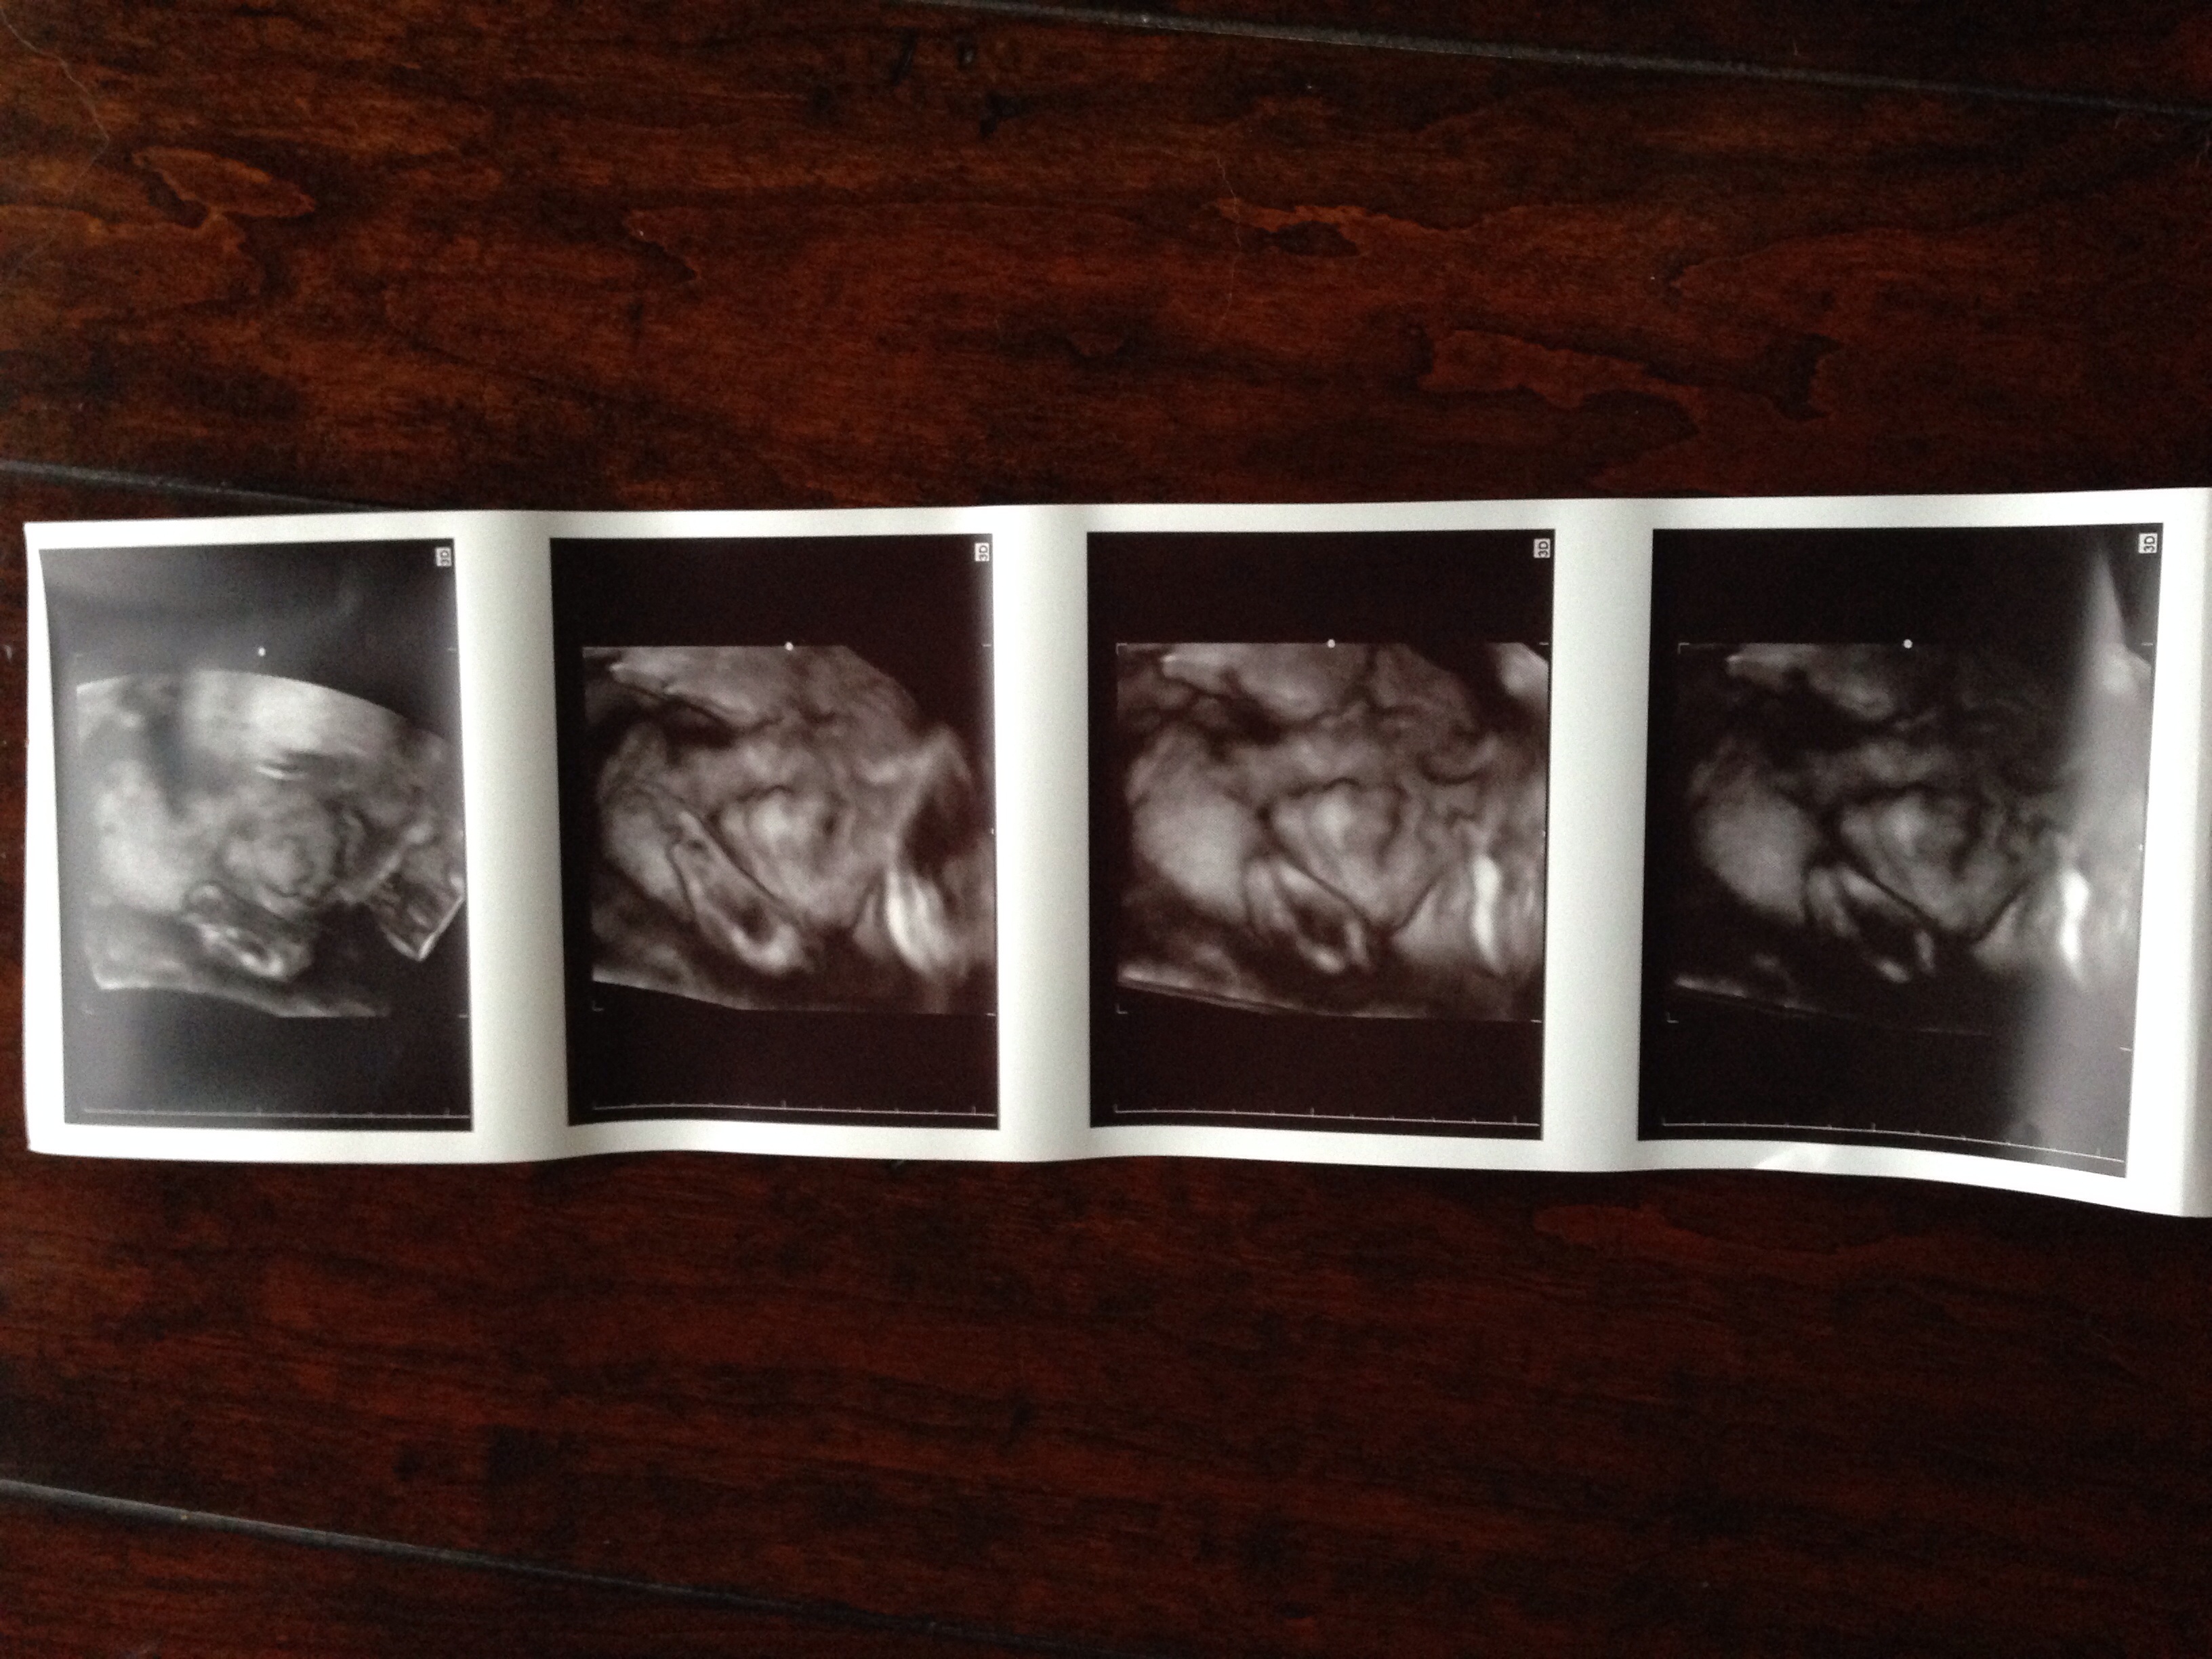

Here's my handsome little man.... He had his hands n feet covering his face whole time but still managed to get some great shots of his cute nose n beautiful lips :)